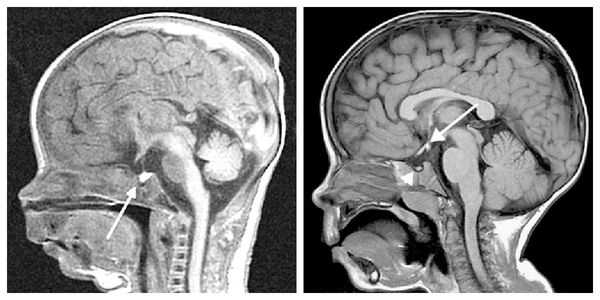

- рентген, КТ или МРТ турецкого седла (области черепа, где находится гипофиз);

- КТ или МРТ головного мозга для исключения опухолевого процесса.

Рентгенография турецкого седла выявляет его детскую форму («стоячий овал») и широкую (т. н. ювенильную) спинку. При увеличении размеров турецкого седла и наличии участков обызвествления, в первую очередь, следует думать об опухоли. Рентгенография лучезапястных суставов и кистей позволяет определить рентгенологический («костный») возраст. При гипофизарном нанизме отмечается значительное замедление процессов окостенения скелета.

Для выяснения формы нанизма необходимо исследование инсулиноподобного фактора роста (соматомедина-С), ТТГ, ЛГ, ФСГ, Т3, Т4, кортизола в плазме и моче, антител к тиреоглобулину, микросомальной фракции тироцитов и др. Для исключения опухолевого поражения проводится КТ (МРТ) головного мозга.

- Нейровизуализация. Чтобы обнаружить органические поражения гипоталамо-гипофизарной зоны, проводится рентгенография турецкого седла, МРТ или КТ головного мозга. При необходимости обследование дополняется церебральной ангиографией, электроэнцефалографией.

У некоторых пациентов с мутацией конкретных генов выявляется гиперплазия передней доли гипофиза (аденогипофиза). В процессе жизни может произойти её атрофия вплоть до формирования синдрома "пустого турецкого седла" — недостаточности области головного мозга, где расположен гипофиз. Данный синдром приводит к внедрению мягкой мозговой оболочки в полость турецкого седла, сдавлению и уменьшению гипофиза, что нарушает или полностью прекращает его работу.

При необходимости проводится МРТ головного мозга и гипофиза с контрастированием [6] . Она позволяет исключить или подтвердить наличие объёмных образований области гипофиза и головного мозга.

- МРТ головного мозга. В фазе острого воспаления визуализируется увеличение, неоднородность структуры, размытость контуров гипофиза, утолщение воронки. При переходе процесса в хронический выявляется фиброз и уменьшение гипофиза.